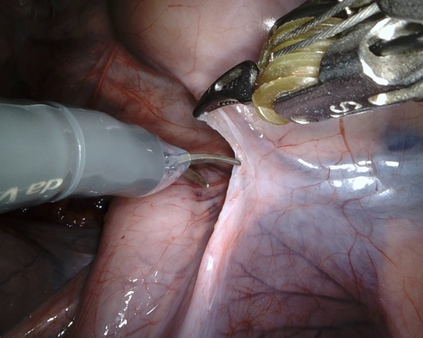

Visual question answering (VQA) in surgery is largely unexplored. Expert surgeons are scarce and are often overloaded with clinical and academic workloads. This overload often limits their time answering questionnaires from patients, medical students or junior residents related to surgical procedures. At times, students and junior residents also refrain from asking too many questions during classes to reduce disruption. While computer-aided simulators and recording of past surgical procedures have been made available for them to observe and improve their skills, they still hugely rely on medical experts to answer their questions. Having a Surgical-VQA system as a reliable 'second opinion' could act as a backup and ease the load on the medical experts in answering these questions. The lack of annotated medical data and the presence of domain-specific terms has limited the exploration of VQA for surgical procedures. In this work, we design a Surgical-VQA task that answers questionnaires on surgical procedures based on the surgical scene. Extending the MICCAI endoscopic vision challenge 2018 dataset and workflow recognition dataset further, we introduce two Surgical-VQA datasets with classification and sentence-based answers. To perform Surgical-VQA, we employ vision-text transformers models. We further introduce a residual MLP-based VisualBert encoder model that enforces interaction between visual and text tokens, improving performance in classification-based answering. Furthermore, we study the influence of the number of input image patches and temporal visual features on the model performance in both classification and sentence-based answering.